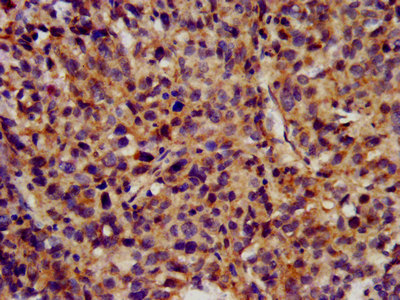

IHC image of CSB-PA621758LA01HU diluted at 1:300 and staining in paraffin-embedded human ovarian cancer performed on a Leica BondTM system. After dewaxing and hydration, antigen retrieval was mediated by high pressure in a citrate buffer (pH 6.0). Section was blocked with 10% normal goat serum 30min at RT. Then primary antibody (1% BSA) was incubated at 4°C overnight. The primary is detected by a biotinylated secondary antibody and visualized using an HRP conjugated SP system.

IHC image of CSB-PA621758LA01HU diluted at 1:300 and staining in paraffin-embedded human pancreatic cancer performed on a Leica BondTM system. After dewaxing and hydration, antigen retrieval was mediated by high pressure in a citrate buffer (pH 6.0). Section was blocked with 10% normal goat serum 30min at RT. Then primary antibody (1% BSA) was incubated at 4°C overnight. The primary is detected by a biotinylated secondary antibody and visualized using an HRP conjugated SP system.